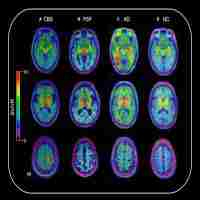

| Abstract | OBJECTIVE 18 F-flortaucipir (formerly 18 F-AV1451 or 18 F-T807) binds to neurofibrillary tangles in Alzheimer disease, but tissue studies assessing binding to tau aggregates in progressive supranuclear palsy (PSP) have yielded mixed results. We compared in vivo 18 F-flortaucipir uptake in patients meeting clinical research criteria for PSP (n = 33) to normal controls (n = 46) and patients meeting criteria for Parkinson disease (PD; n = 26). METHODS Participants underwent magnetic resonance imaging and positron emission tomography for amyloid-β (11 C-PiB or 18 F-florbetapir) and tau (18 F-flortaucipir). 18 F-flortaucipir standardized uptake value ratios were calculated (t = 80-100 minutes, cerebellum gray matter reference). Voxelwise and region-of-interest group comparisons were performed in template space, with receiver operating characteristic curve analyses to assess single-subject discrimination. Qualitative comparisons with postmortem tau are reported in 1 patient who died 9 months after 18 F-flortaucipir. RESULTS Clinical PSP patients showed bilaterally elevated 18 F-flortaucipir uptake in globus pallidus, putamen, subthalamic nucleus, midbrain, and dentate nucleus relative to controls and PD patients (voxelwise p < 0.05 family wise error corrected). Globus pallidus binding best distinguished PSP patients from controls and PD (area under the curve [AUC] = 0.872 vs controls, AUC = 0.893 vs PD). PSP clinical severity did not correlate with 18 F-flortaucipir in any region. A patient with clinical PSP and pathological diagnosis of corticobasal degeneration had severe tau pathology in PSP-related brain structures with good correspondence between in vivo 18 F-flortaucipir and postmortem tau neuropathology. INTERPRETATION 18 F-flortaucipir uptake was elevated in PSP versus controls and PD patients in a pattern consistent with the expected distribution of tau pathology. Ann Neurol 2017;82:622-634. |